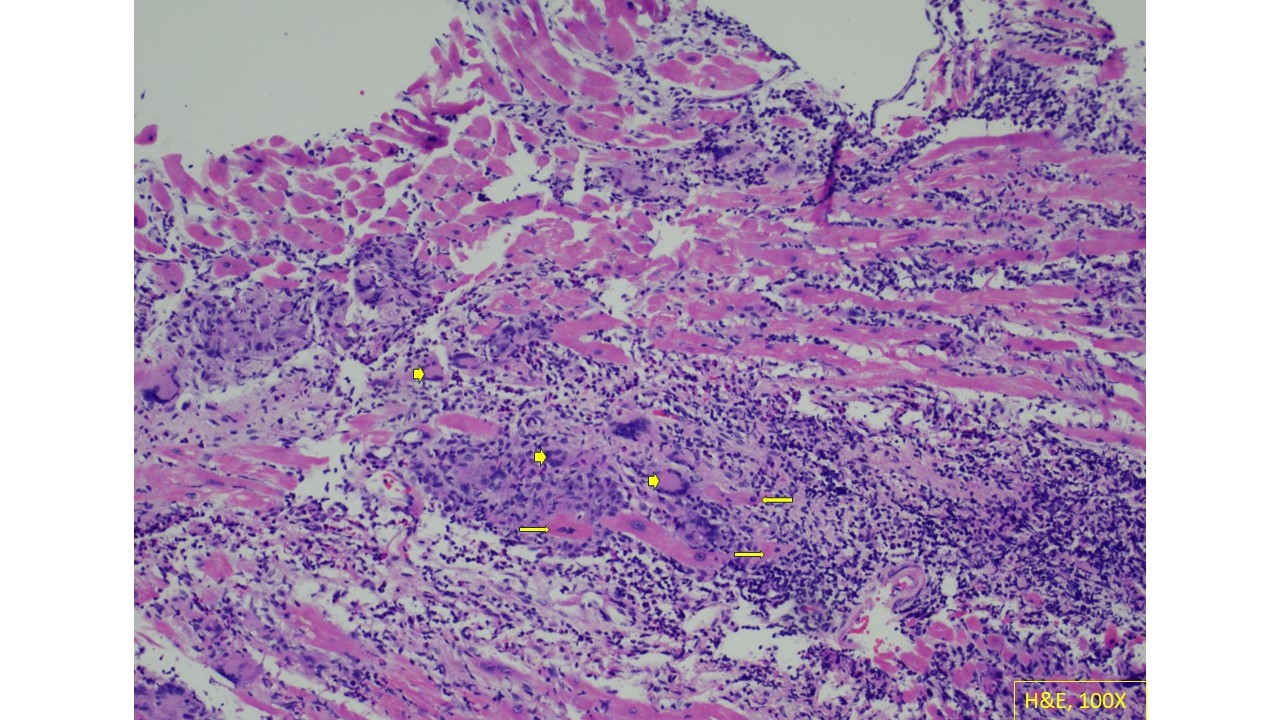

Case presentation: A 66-year-old female with type II diabetes, obesity, and coronary artery disease (CAD), presented with dyspnea, orthopnea, epigastric pain, and hypotension. Laboratory findings showed troponin at 2301 ng/L and lactic acidosis, with nonspecific ST changes on EKG prompting treatment for acute coronary syndrome (ACS). She was started on dobutamine and admitted to the cardiac ICU for cardiogenic shock. An echocardiogram revealed left ventricular ejection fraction (LVEF) of 25% with diffuse hypokinesis. She underwent coronary angiography which showed no significant obstructive CAD. She remained in cardiogenic shock despite inotropic support, prompting placement of an Impella and endomyocardial biopsy. Pathology revealed diffuse interstitial giant cells and multifocal cardiomyocyte necrosis, consistent with GCM. She was treated with pulse-dose steroids, tacrolimus, and placed on the heart transplant list. After 14 days with Impella 5.5 support, her LVEF improved to 45%. She has since been managed with mycophenolate, prednisone, and guideline-directed medical therapy for heart failure.